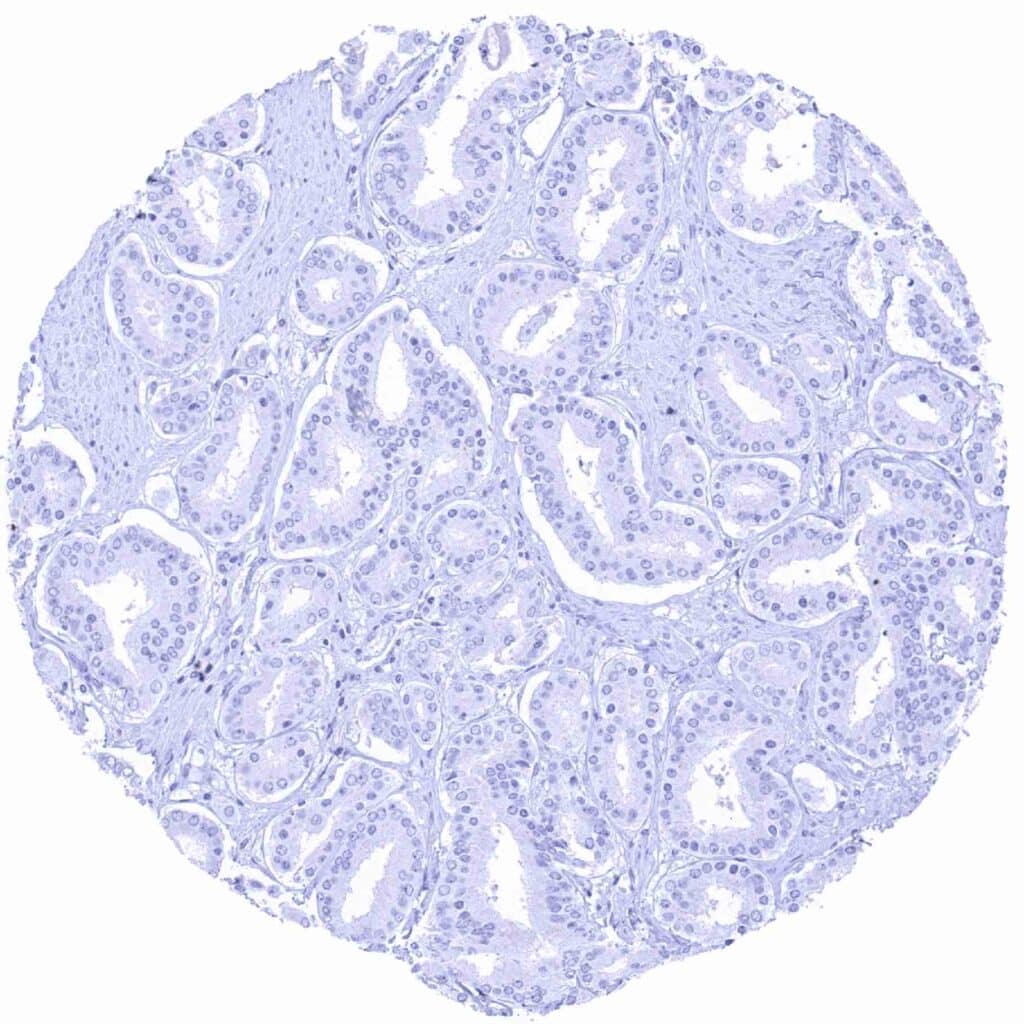

Pancreas – PAX8 negative ductal adenocarcinoma